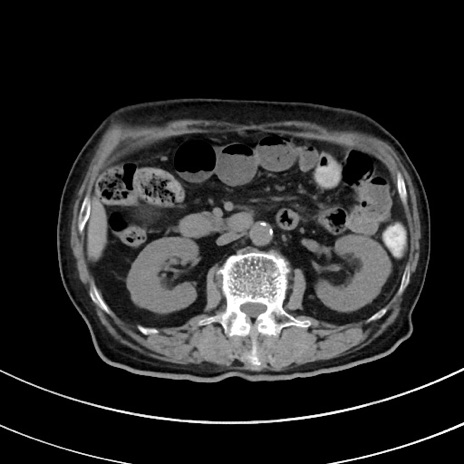

症例33(横断像)

【症例】70歳代 女性

【主訴】心窩部痛

【現病歴】延髄病変の精査・加療にて神経内科入院中。本日より心窩部痛あり。

【身体所見】右下腹部を中心に圧痛と反跳痛あり。

【データ】WBC 10900、CRP 0.02